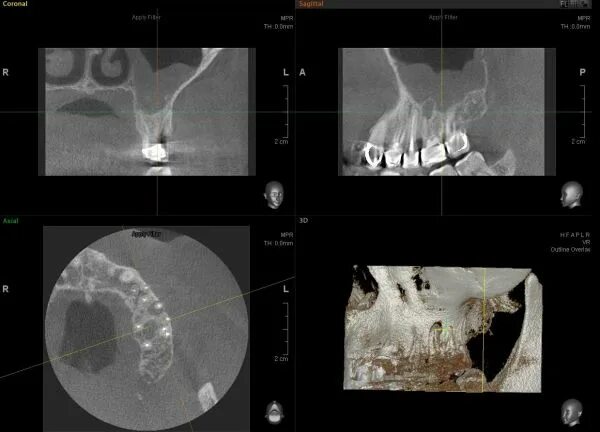

Picasso кт